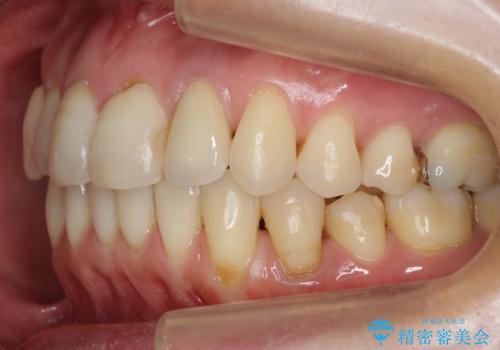

埋まっている奥歯を引っ張り出す インビザライン矯正

- 前歯のがたつきと左下の歯がうまっているとのことで、矯正治療を希望されました。

埋まっている奥歯を並べることで、その後ろの倒れ込んだ歯を整直させることができました。

引っ張り出すことはマウスピース矯正では難しい為、埋まっている歯を並べるスペース確保と、引っ張り出すのに、ワイヤーを用いた部分矯正を行なっています。

上の歯はマウスピース矯正で、奥歯を後ろに下げて、左のかみ合わせのズレを直しています。

上下とも非抜歯で並べています。